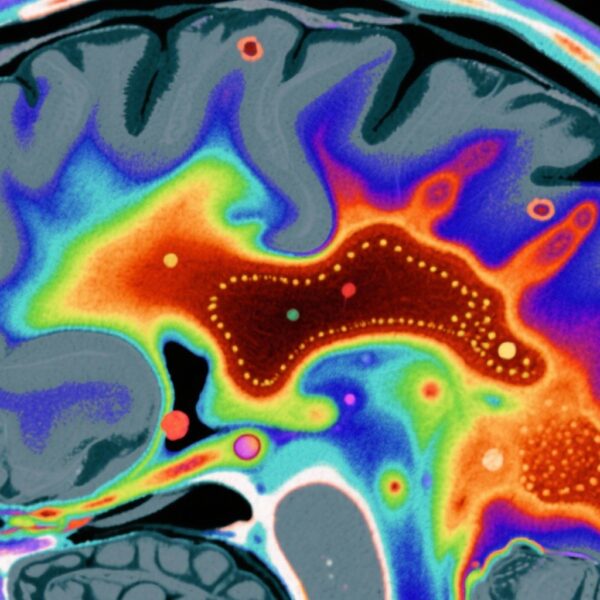

本研究利用了《精神和物质使用障碍患病率研究》的数据,该研究是一个具有全国代表性的非老年人美国成年人样本(N=4,764)。参与者接受了由临床医生管理的《DSM-5结构化临床访谈》(SCID-5)评估,以确定过去一年和终身SSDs(包括精神分裂症、分裂情感性障碍和短暂性精神分裂症)的患病率,以及识别阳性精神病症状。

研究显示SSD患病率存在显著的种族差异。非西班牙裔黑人的患病率为4.1%,显著高于非西班牙裔白人的1.2%。调整年龄和性别后,黑人参与者的SSD患病率是3.49倍(95% CI: 1.37–8.91),精神病症状的患病率是2.04倍(95% CI: 1.15–3.63)。非西班牙裔多族裔个体的SSD患病率为5.6%,调整后的OR为4.59(95% CI: 1.53–13.76)。

关键的是,在进一步调整社区SVM评分后,黑人种族与SSD之间的关联显著减弱(调整后的OR=2.49,95% CI: 0.63–9.90),并失去了统计学意义。类似地,精神病症状的差异也减少了(调整后的OR=1.69,95% CI: 0.83–3.44)。相比之下,对于非西班牙裔多族裔个体,即使调整了SVM评分,SSD的差异仍然显著(调整后的OR=3.95,95% CI: 1.30–12.00),尽管有所减弱。